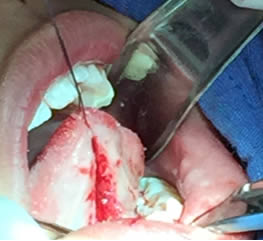

• Se pasa una sutura sin anudar en la punta de la lengua para traccionar la misma y facilitar las maniobras quirúrgicas. Posteriormente se utilizan dos pinzas de mosco, una curva y una recta pinzando el frenillo en su borde superior e inferior para limitar sus bordes. Figuras 3 y 4.

Figura 3. Sutura sin anudar en punta de la lengua

Figura 4. Pinzado del frenillo